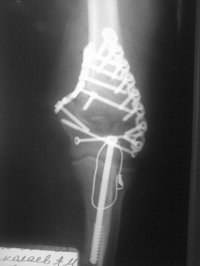

Риторический вопрос - если возможно, то хотелось бы посмотреть все снимки на этапах лечения. В данном сегменте даже при очень сложных переломах, при использовании накостного остеосинтеза достигаются очень приличные результаты. Привожу рентгенограммы пациентки. Операция проведена через 3 недели после травмы. На сегодняшний момент 3 недели после остеосинтеза. Движения сгибание до 60 градусов, разгибание 150-160. Мое мнение, что спицы и 45 суток в гипсе это несколько грубо для такого "капризного" локтевого сустава.

Имя     : локоть 1.jpg